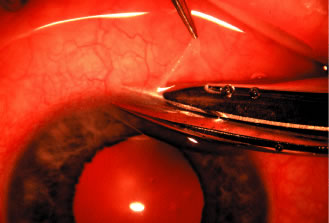

episclera are not adequate sites for fixation.  Fig. 5. Paracentesis. It is advisable to perform a keratostomy in virtually every

patient who is undergoing an intraocular glaucoma procedure. A 25-gauge, short, sharp, disposable needle is useful for this purpose and allows

easy insertion of a 30-gauge blunt irrigating needle later in the

procedure. To ensure that the needle does not damage the iris or lens, it

must be introduced in a plane parallel to the iris. Penetration

of the cornea is achieved by indentation of the cornea that is caused

by pressure on the syringe, pushing the syringe and needle against the

globe. Penetration is not achieved by angulating the needle. (Spaeth GL. Glaucoma surgery. In Spaeth GL (ed). Ophthalmic Surgery: Principles

and Practice, 2nd ed. Philadelphia: WB Saunders, 1990.) Fig. 5. Paracentesis. It is advisable to perform a keratostomy in virtually every

patient who is undergoing an intraocular glaucoma procedure. A 25-gauge, short, sharp, disposable needle is useful for this purpose and allows

easy insertion of a 30-gauge blunt irrigating needle later in the

procedure. To ensure that the needle does not damage the iris or lens, it

must be introduced in a plane parallel to the iris. Penetration

of the cornea is achieved by indentation of the cornea that is caused

by pressure on the syringe, pushing the syringe and needle against the

globe. Penetration is not achieved by angulating the needle. (Spaeth GL. Glaucoma surgery. In Spaeth GL (ed). Ophthalmic Surgery: Principles

and Practice, 2nd ed. Philadelphia: WB Saunders, 1990.)

We prefer to use a new, sharp, short, disposable 27-gauge needle on a 2- or 5-ml

syringe. The needle is held, bevel up, absolutely parallel to

the iris surface. In an eye with an iris bombe or a flat anterior chamber, the

needle actually may be pointing anteriorly. The tip of the

needle is placed against the cornea in the desired position, and the globe

is pulled by the fixating hand in the direction opposite to that

in which the needle is pointing. For example, if the needle is held horizontally, at

the 3 o'clock position of the left eye, then the sclera

is grasped at the 3 o'clock position and pulled laterally (temporally) (see Fig. 5). The needle tip enters the cornea. If there is normal or elevated pressure

and the chamber is deep, the needle penetrates the cornea after making

a paracentesis that is approximately 1 to 2 mm long. If the eye is

soft or the chamber is shallow, the needle remains in the cornea and

does not penetrate the anterior chamber. This position is desirable in

cases in which the cornea is thin, such as in the buphthalmic eye. If

the intracorneal track is longer than 2 mm, then the needle and syringe

are depressed back toward the apex of the orbit; they are depressed

toward the floor of the operating room (see Fig. 5, top right). The tip of the needle must not be angled toward the iris-lens; it must

be kept parallel to the iris. As the needle and syringe are pushed

toward the floor, the needle changes the curvature of the cornea, permitting

it to enter the anterior chamber when advanced. The needle is advanced

by a combination of pulling the globe and pushing the syringe. The

importance of firm fixation and of introducing the needle against

traction provided by the fixation must be stressed. Also, it is essential

that the needle not be angled toward the iris, but kept parallel

to the iris surface. Once the needle enters the anterior chamber, it is more clearly visible

than when it is intracorneal (see Fig. 5, bottom right). The tip is advanced carefully about 1 to 3 mm, until the surgeon is

sure that the endothelium has been completely penetrated. The needle is

then withdrawn. If the paracentesis has been made with a no. 25 needle, a no. 30 blunt-tipped

needle can be introduced later with ease. If the cornea is especially

thin or if the surgeon wishes the fit to be especially tight, a 30-gauge

needle should be used for the paracentesis. When re-entering the paracentesis track, the blunt needle must be directed

exactly parallel to the original track and must hug the posterior (internal, deep) aspect

of the track. Often, the neophyte struggles unnecessarily

to get the no. 30 blunt-tipped needle into the anterior chamber

through a no. 27-size paracentesis. However, when the blunt-tipped 30-gauge

needle is angled in the direction of the floor, that is, toward

the iris, and slid along the internal aspect of the paracentesis, it

enters gracefully. Alternatively, use a sharp 27-gauge needle for